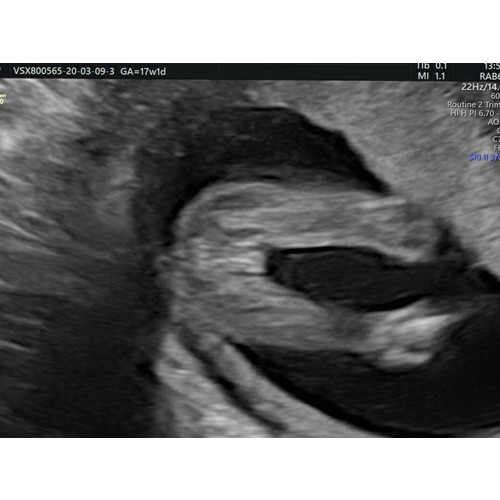

Dit is de echo foto van ons meisje bij 17 weken. 馃挆